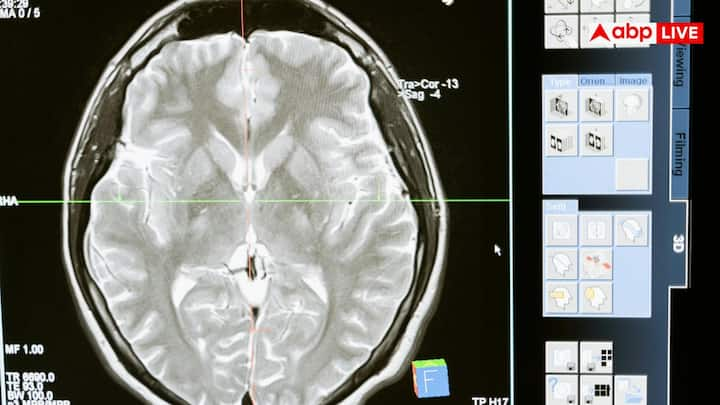

ब्रेन कैंसर की शुरुआती पहचान इसलिए मुश्किल होती है क्योंकि इसके कई लक्षण सामान्य सिरदर्द जैसे लगते हैं. यही वजह है कि लोग शुरुआत में इन्हें गंभीरता से नहीं लेते. असली अंतर इसके पैटर्न, तीव्रता और साथ आने वाले अन्य लक्षणों में छिपा होता है.